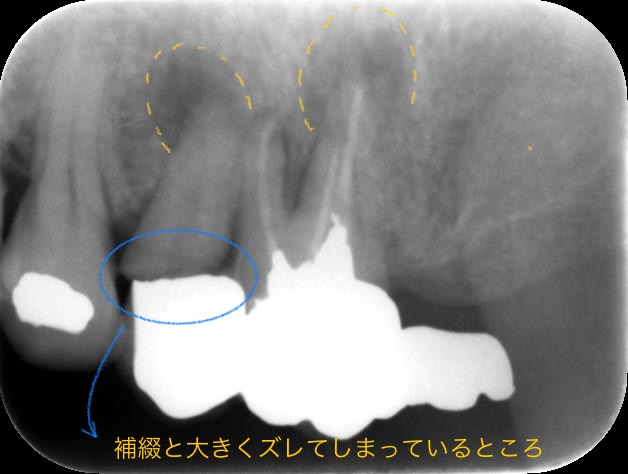

こちらが局所のレントゲン写真です

根っこの先に膿が溜まってしまい、根尖病変ができてしまっています。また、5番目は上の補綴と大きくズレてしまっているため、破折してしまっている可能性もあります。

ブリッジにぐらつきがあるのは本来2本の歯で支えていた上の補綴がほぼ6番目だけの力で支えている状態になってしまっているためです。